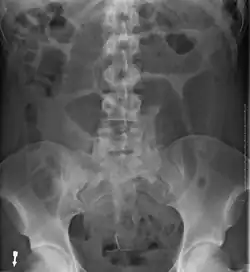

- Abdominal x-ray – tire-like shadow arising from the right iliac fossa and passing to the left

Plain X ray of a cecal volvulus